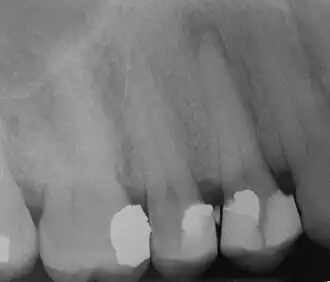

Rozpoznanie torbieli korzeniowej opiera się na badaniu przedmiotowym oraz radiologicznym. Najczęściej wykonuje się zdjęcie pantomograficzne oraz zdjęcia wewnątrzustne. W obrazie RTG torbiel korzeniowa widoczna jest w postaci jednolitego przejaśnienia o gładkich zarysach, wyraźnie odgraniczonego od otoczenia. Korzenie zębów sąsiadujących z torbielą są rozsunięte przez powiększającą się zmianę. Torbiel przybiera w szczęce kształt kulisty, w żuchwie zaś owalnie spłaszczony. W celu określenia wielkości i topografii torbieli oraz wyboru drogi operacyjnej pomocne mogą okazać się badanie ultrasonograficzne, scyntygrafia kości, technika rezonansu magnetycznego. Ostatecznym potwierdzeniem rozpoznania jest badanie cytologiczne zaaspirowanej treści zmiany oraz badanie histopatologiczne wyłuszczonego mieszka torbieli.